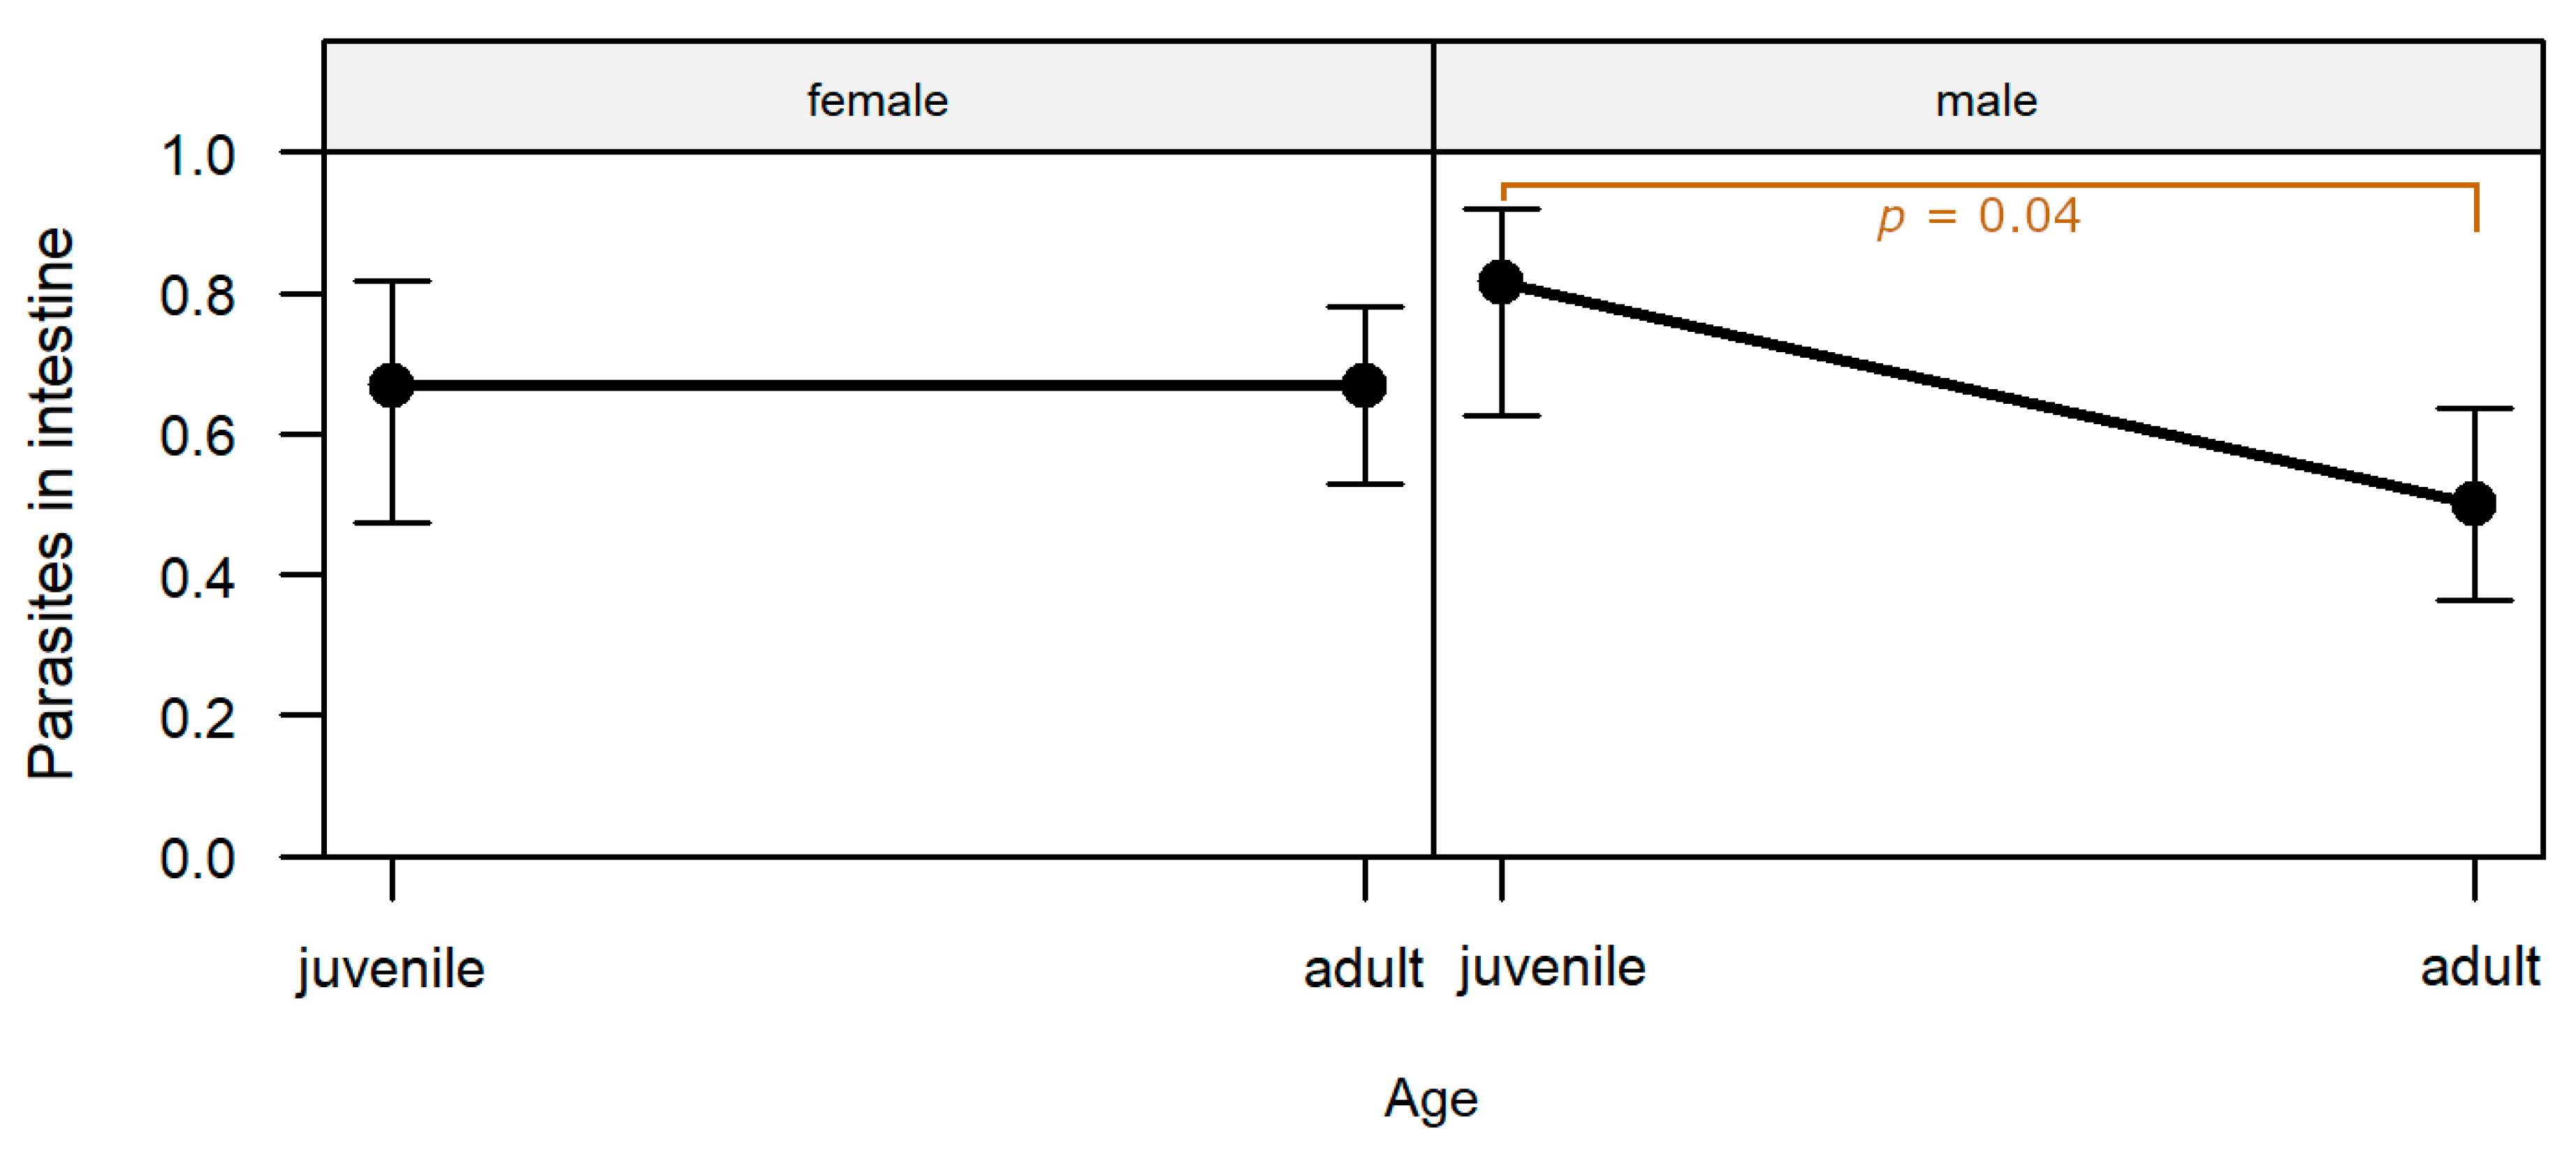

Intestine: The most common finding in histopathological analyses, which was observed in 99 out of 155 investigated hares (63.9%), was the detection of parasites or parasite stages in the intestine. Mainly different stages of protozoal organisms were found (74.7%, n = 74) and either detected in the intestinal epithelium (n = 35,

The presence of parasites or parasite stages in the intestine was significantly affected by the interaction of sex and age (

p = 0.048;

Table S1). Parasites were detected significantly more frequently in male juveniles than in male adults (post-hoc test,

p = 0.038;

Table S2;

Figure 6).

In 20 animals (20.2%), enteritis and parasites or parasite stages were detected simultaneously in histopathological investigations.

An activation of the regional immune system in the form of hyperplasia of mesenteric lymph nodes or Peyer’s patches was diagnosed concurrently with intestinal parasites in 47 hares (47.5%).

71]. This might be explained by the naïve immune system of juveniles, resulting in higher infection prevalence and oocyst excretion rates. In the present study, however, significantly higher frequencies of coccidiosis were only observed for juvenile males but not for females. One explanation might be a limited validity of this histopathologically generated parasitological data, as only limited areas of the intestine could be examined. Previous studies in other species describe an effect of hormones on susceptibility to parasitic infections, with androgens increasing infection rate with parasites and inhibiting antibody formation [

84,

85,

86]. In other parts of Germany, females were infected as often as males with